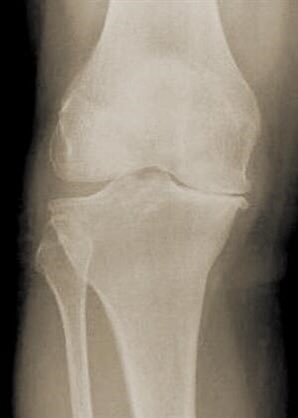

- يشترط عمل أشعة رنين مغناطيسي لتشخيص خشونة المفاصل .

لايشترط ذلك ويكتفى بعمل أشعة سينية في وضعيات معينه كالوقوف لمعرفة مدى الضرر الحاصل على المفصل .